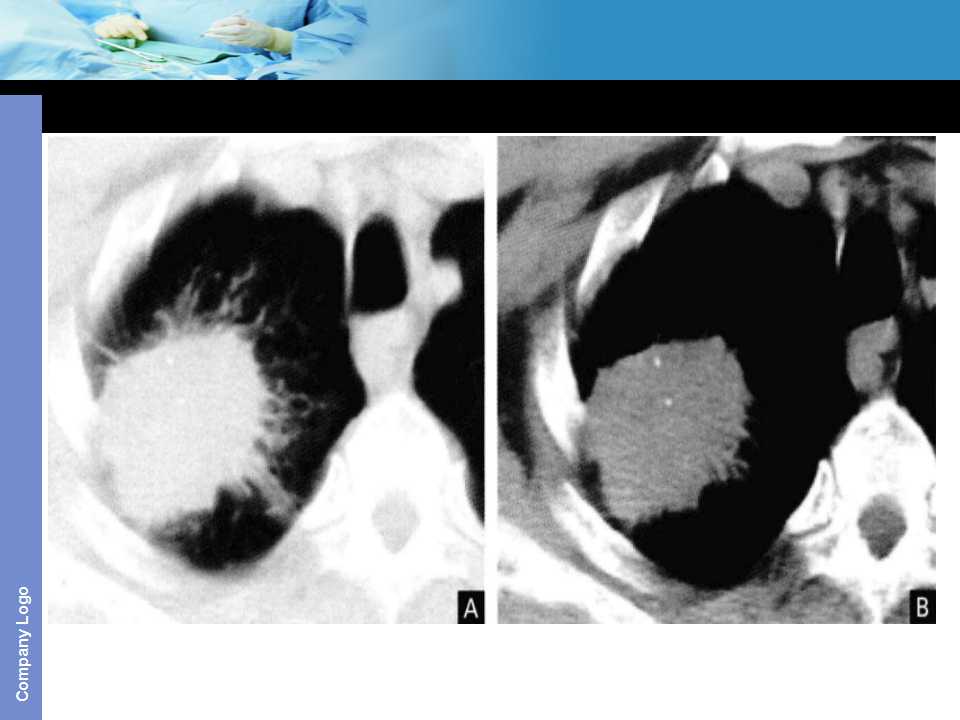

肺癌影像诊断